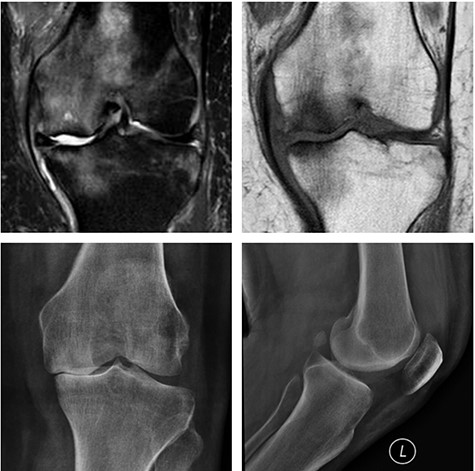

Top: anterior (left) and lateral view (right) X-ray images of the immediate postoperative period (medial UKA); Bottom: anterior (left) and lateral view (right) X-ray images of the same patient with 5 months of follow-up with tibial component loosening.